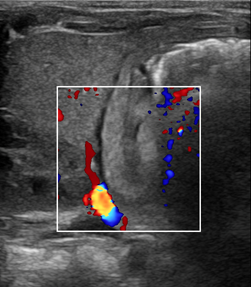

患儿女,33天,足月儿,因“反复严重呕吐30+天”于我院小儿外科门诊就诊,遂建议超声检查排除“先天性肥厚性幽门狭窄”。超声所见:十二指肠呈空虚状态。幽门壁肌层最厚约4.4mm,幽门最大横径约14mm,幽门管长约19mm(图1-3),幽门管腔变窄,胃内查见液性及稍强回声潴留物,胃内容物通过幽门管受阻(图4)。超声诊断为“先天性肥厚性幽门狭窄”。遂入院手术治疗,术中及术后病理证实为CHPS。

图3:幽门CDFI